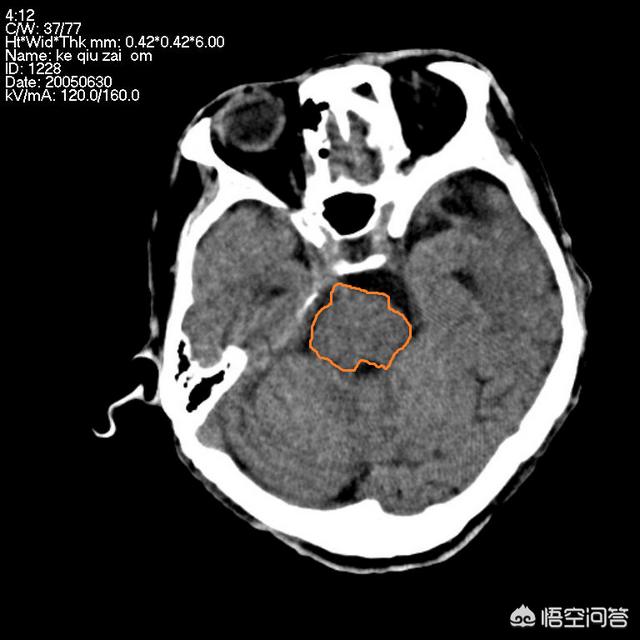

脳梗塞は脳梗塞の略称で、一般的に梗塞部位と梗塞部位の大きさによって、その予後は大きく異なり、脳梗塞が大きい患者さんでは、血栓摘出治療、血栓溶解治療などの積極的な治療を行っても、一般的に予後が良くないが、海綿状脳梗塞は予後が良いが、再発防止に注意する必要がある。他のタイプの脳梗塞の予後は、治療が適時であるかどうか、適時の診察、積極的なリハビリテーション、治療が可能であるかどうかによって決まりますが、完治は難しく、良くなるまでには長い時間がかかり、年単位で計算されます。

脳梗塞が回復できるかどうかは、脳梗塞の部位と範囲によります。後遺症の原因として多いのは、主に「内果後縁」と呼ばれる場所で、これは手足の活動と同様に片側の顔面筋が支配されるためで、口角が曲がってしまう、片麻痺が起こる、もう一つは「脳幹」です。もう一つは「脳幹」で、その名の通り、木の幹のようなもので、より重要なため、常に脳組織の中心にあり、この場所は機能が密集しており、少し梗塞を起こすと、嚥下障害、片麻痺、複視、斜頸などを引き起こし、重症になると昏睡や植物状態になる。梗塞後、理解できるが話せないものを「運動性失語症」、理解できないが話せるものを「感覚性失語症」と呼ぶ。

梗塞が大きければ、患者の意識に影響を及ぼす。もちろん、「ラクナ脳梗塞」と呼んでいる、重要な機能部位でない、側脳室周辺部や小脳などに小さな梗塞もあり、多くの患者さんは自覚症状がないか、手足のしびれやめまいなどで済むことがあります。しかし、この病気は再発しやすく、1年後の再発率は30%ですから、回復できた人も軽視してはいけません。二次予防、定期的な運動、禁煙・禁酒、高血圧や糖尿病のコントロールなどをしっかり行い、再発率を下げましょう。